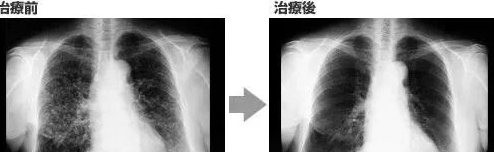

一名广泛期小细胞肺癌患者,在进行4个疗程化疗和4次高度活化NK细胞临床干预后,患者第一次进行治疗后的CT复查,结果显示,肿瘤缩小到了原来的1/8。而且距发病第六年的CT复查中,仍旧没有发现任何异常及复发的迹象。